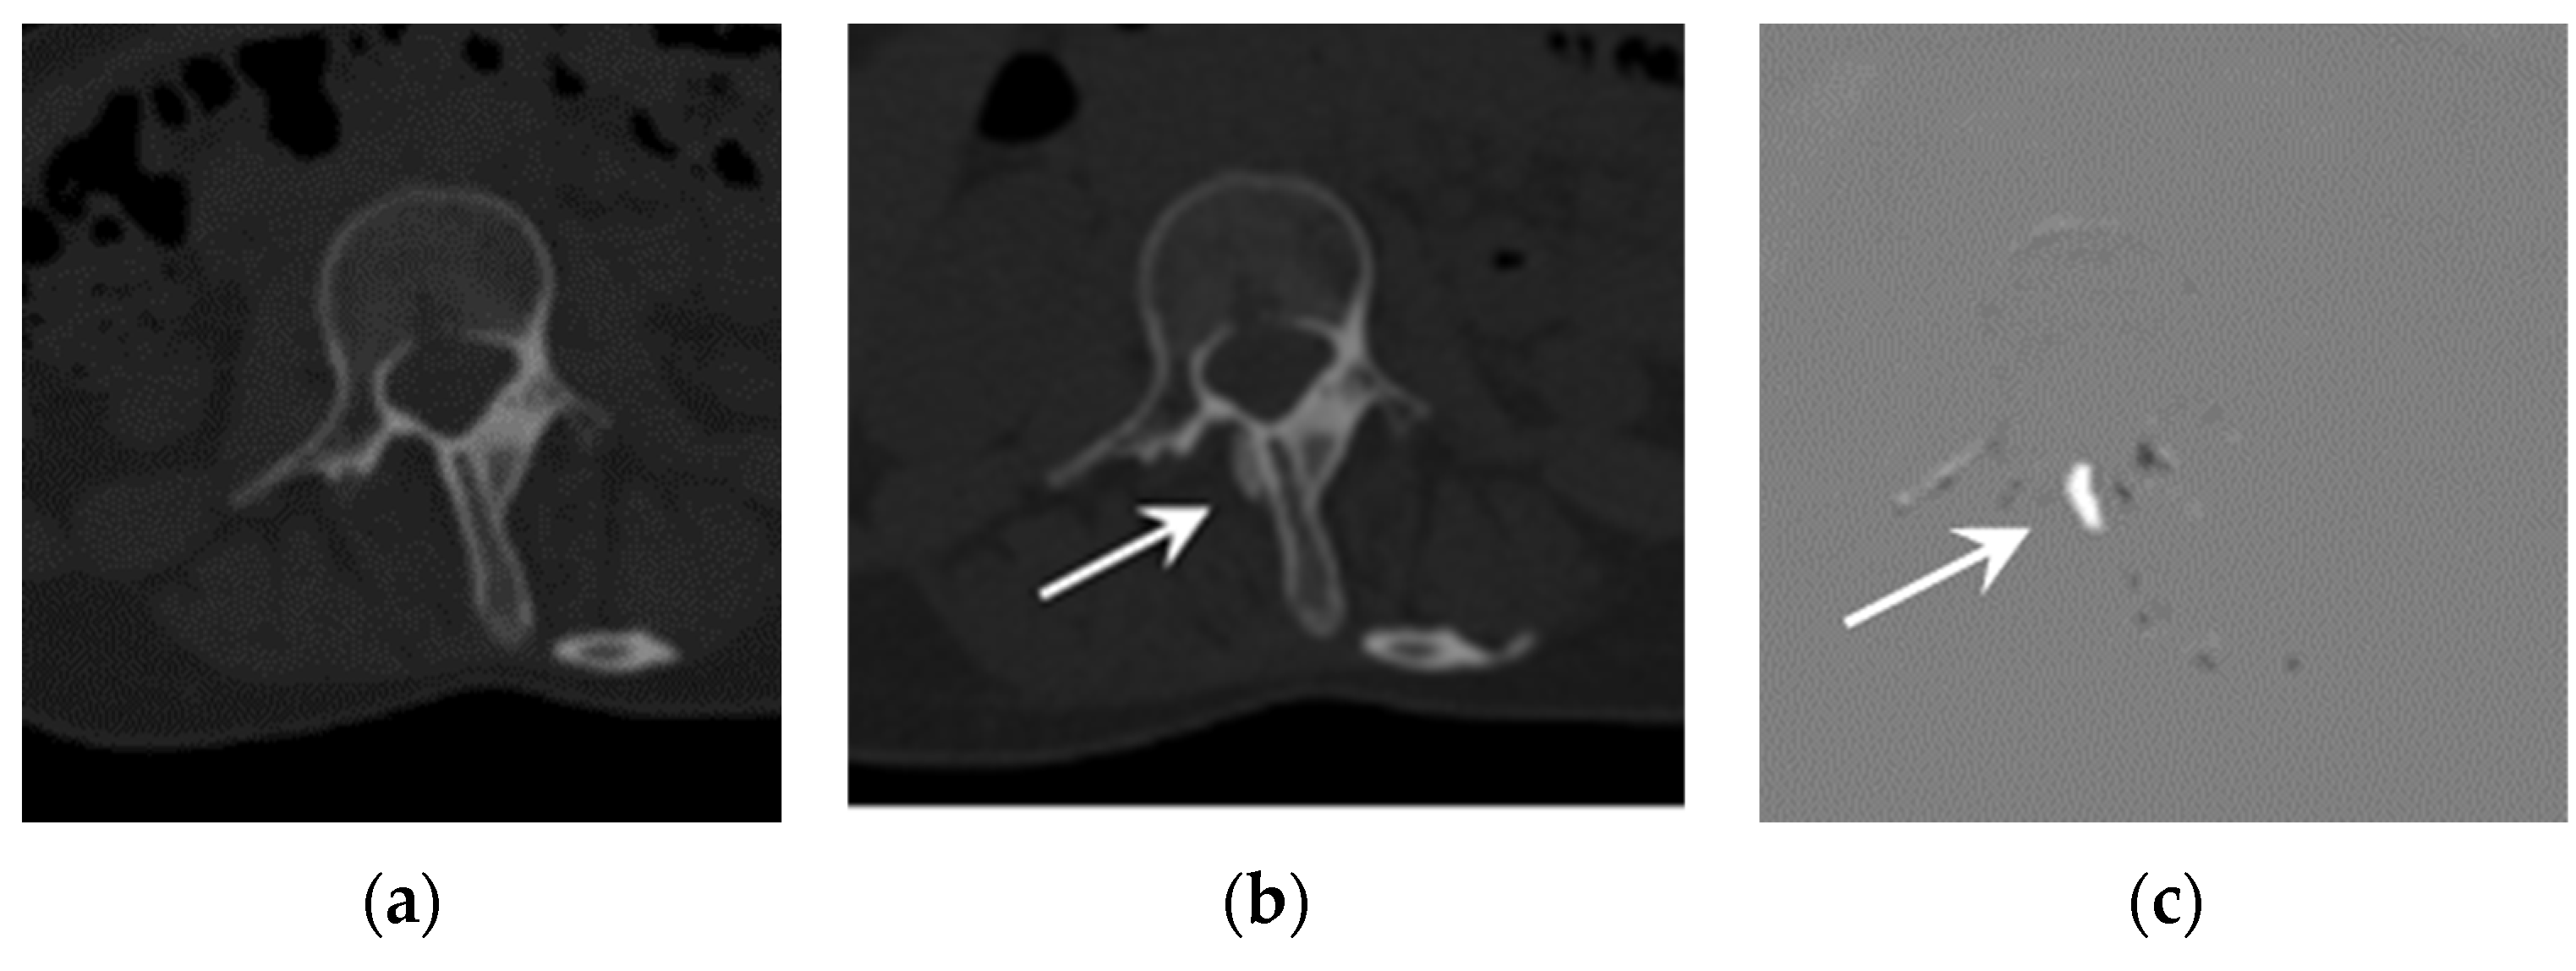

Figure 1.

Example of an emerging lesion. CT images of a 25-year-old FOP patient: (a) previous CT image, (b) current CT image, and (c) TS (subtraction) image. The emerging lesion adjacent to the thoracic spine (arrow) is difficult to detect on the current CT image, but is clearly visible in the TS image.